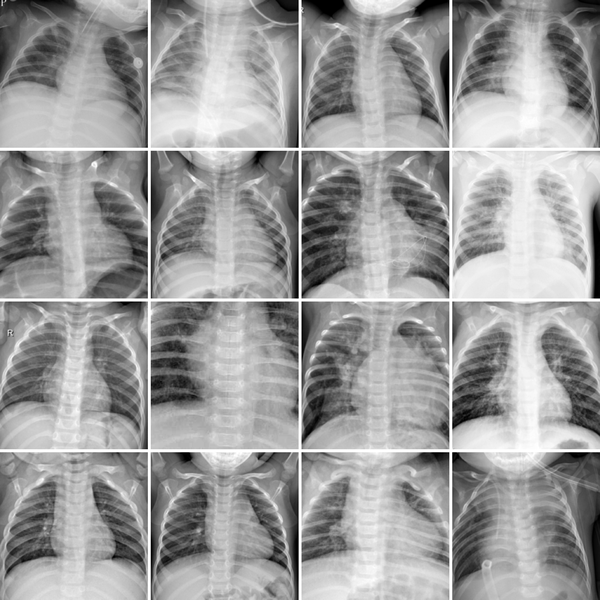

We use a subset of the MedMNIST V2 collection [37], which provides a variety of biomedical image-classification datasets: seven 2D subsets and five 3D subsets from various imaging modalities, as summarized in Table 1. Visual examples of the selected datasets are shown in Figure 1. Although the MedMNIST V2 collection provides datasets in various resolutions (up to 224 for 2D datasets and up to 64 for 3D datasets), we use the smallest available size, namely 28×\times28 for 2D datasets and 28×\times28×\times28 for 3D datasets, to ensure that all experiments can be run in a single GPU setup.

Figure 1: Overview of the 12 selected datasets from the MedMNIST V2 collection used in this study. Each sub-figure shows some representative example images along with the dataset name, imaging modality, and classification task. For the 3D datasets, the middle slices from random samples are shown.